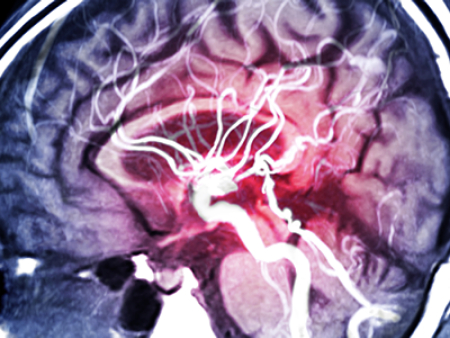

آنژیوگرافی مغزی (Cerebral Angiography) یک روش تصویربرداری پیشرفته است که با استفاده از اشعه ایکس و ماده حاجب، تصاویر دقیقی از عروق خونی مغز، گردن و سر ارائه می‌دهد. این روش به پزشکان کمک می‌کند تا ناهنجاری‌های عروقی مانند تنگی، انسداد، آنوریسم یا مالفورماسیون‌های شریانی-وریدی را تشخیص دهند.

معمولاً از طریق شریان فمورال (کشاله ران) یا رادیال (مچ دست) کاتتر وارد می‌شود. ناحیه بی‌حس شده، کاتتر به عروق گردن و مغز هدایت می‌گردد، ماده حاجب تزریق شده و تصاویر اشعه ایکس گرفته می‌شود. پروسیجر حدود ۱-۲ ساعت طول می‌کشد و اغلب سرپایی است.

• تصاویر توسط رادیولوژیست یا نورورادیولوژیست بررسی می‌شود تا ناهنجاری‌هایی مانند تنگی، انسداد، آنوریسم، AVM یا خونریزی شناسایی گردد.